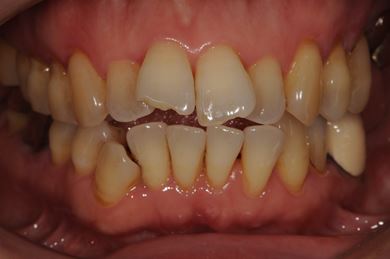

インプラントの症例写真 IMPLANT

インプラント治療+ソケットリフト+GBR

| 性別/年齢 | 女性 / 55歳 | ||||||||||||||||||||||||||||||||

| 主訴 | 奥歯が3本抜歯されてしまったあとにインプラントを入れたい。 | ||||||||||||||||||||||||||||||||

| 治療内容 | インプラント3本(ソケットリフト、GBR)、ハイブリッドセラミック3本 | ||||||||||||||||||||||||||||||||

| 総治療費 | 1,295,300円 | ||||||||||||||||||||||||||||||||

| 治療期間 | 8ヶ月 |